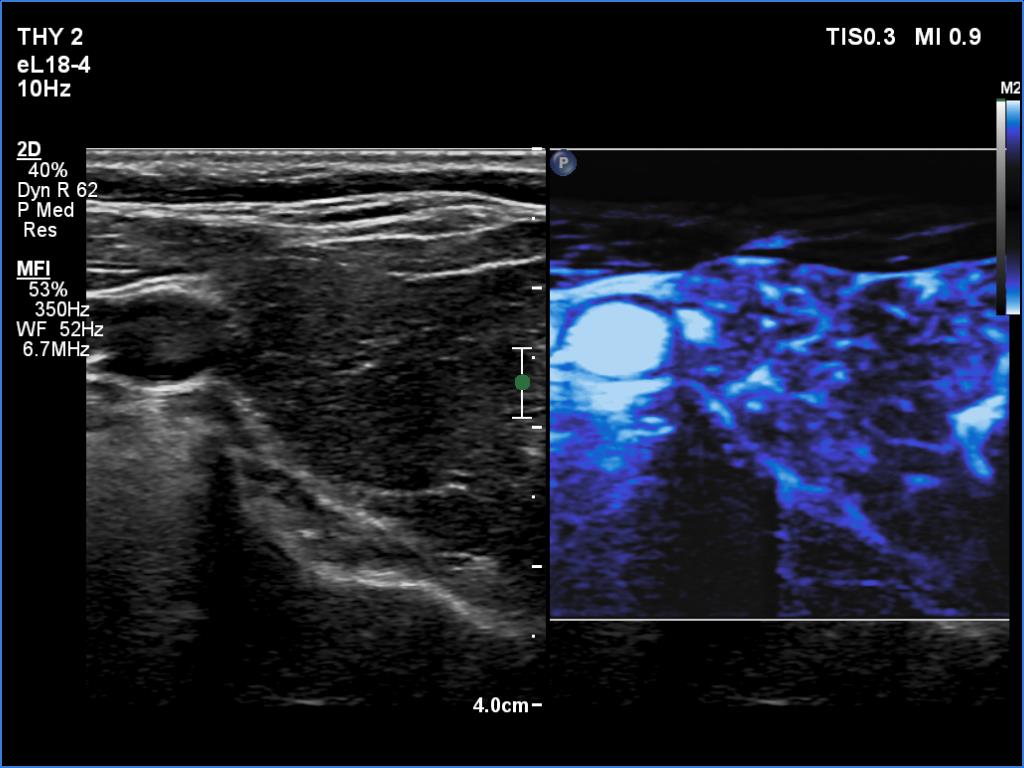

Right lobe, longitudinal scan

Right lobe, transverse scan, microflow imaging. The distribution of vessels is even.